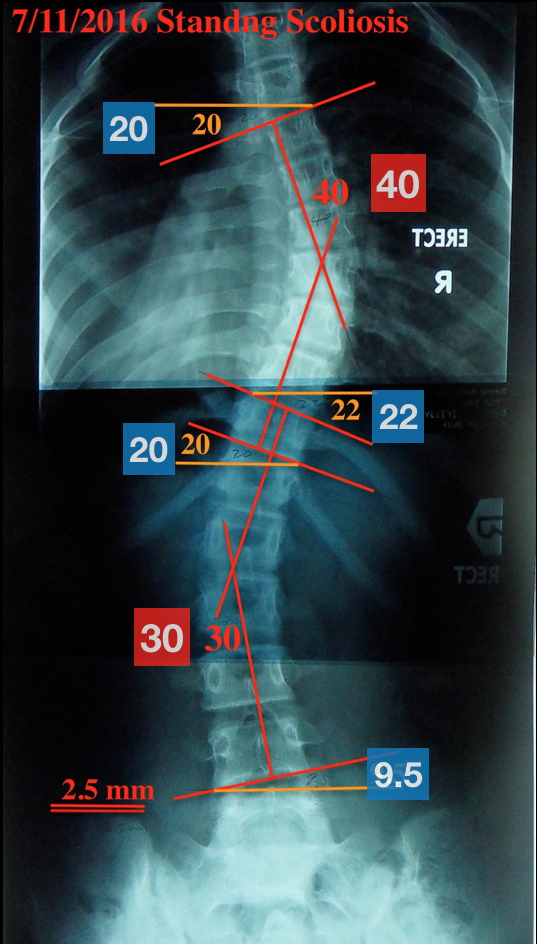

這個個案為13歲女性來自香港,家長於2016年初,發現該個案有高低肩的問題,2016年6月學校健康檢查時發現疑似有脊椎側彎,於2016年7月11日到骨科拍攝X光片,確診為脊椎側彎,度數分別為胸椎40度、腰椎30度(下圖)。![]() |

| 胸椎側彎40度 腰椎側彎30度 |

由X光片(下圖)來分析,40度胸椎凸向右側,最凸點約在胸椎第8節,30度腰椎凸向左側,最凸點約在腰椎第2節,三節最斜的椎體分別為胸椎第5節、胸椎11節、腰椎第4節,其中以胸椎第五及第11節的傾斜角度最明顯,分別為20度及22/20度,度數當接近(藍色區塊)。

| 三節最傾斜的椎體為胸椎第5節、第11節及腰椎第4節,傾斜角度以第一及第二節傾斜椎體的角度最明顯,分別為20度、22/20度 |

我們總共治療了25天,共39次治療,在治療完第36次(23天)後,因表現得比較穩定,我們決定拍攝X光片(下圖右),以確認該個案在這段期間的學習成果。胸椎側彎由40度降為31度,腰椎側彎由30度降為25度,三節最斜的椎體主要是胸椎第11節(也就是第二節斜面)下降最多,第一節最傾斜的椎體些微減少,而第三節傾斜的椎體則是些微增加,骨盆高低差異也些微縮小。